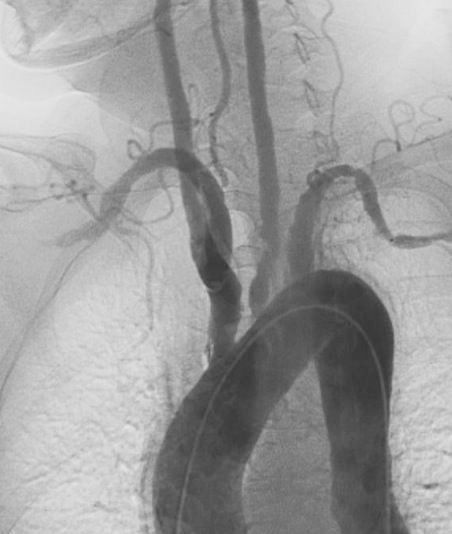

Takayasu arteritis